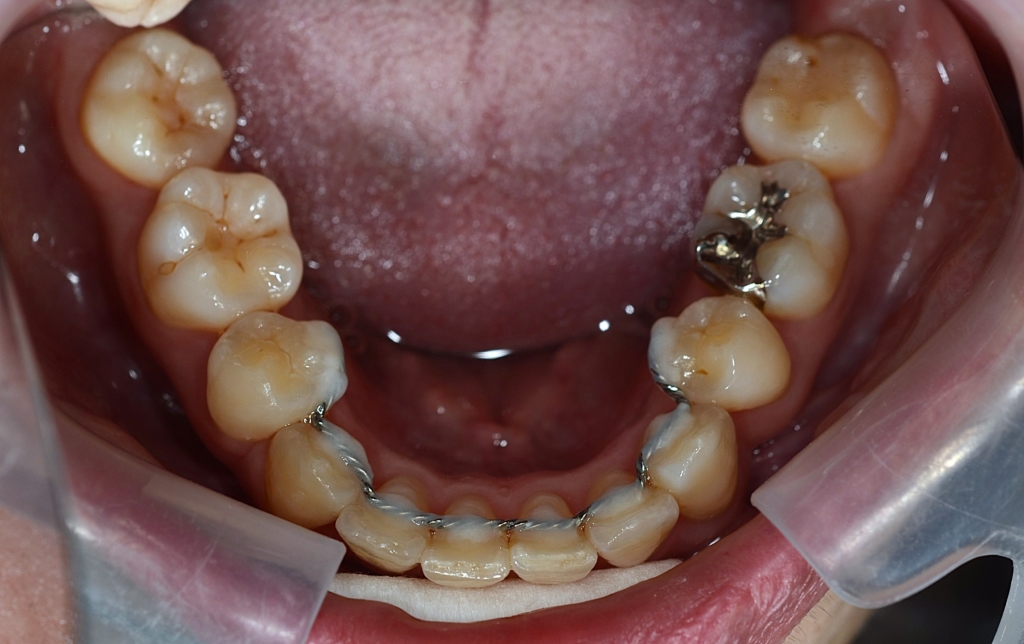

マルチブラケットシステム(ハーフホワイトtype)で矯正を開始。

*ハーフホワイトtype:上下とも歯の表側に白いブラケットを付けて、上には白いワイヤー&下には銀色のワイヤーを用いたストレートワイヤーによる歯列矯正

緑色の丸で囲んだ中にある「下の奥歯から上の前歯にかかる矯正用のゴム」が顎間ゴムです

【保定】 上下ともフィックスタイプ&クリアリテーナー